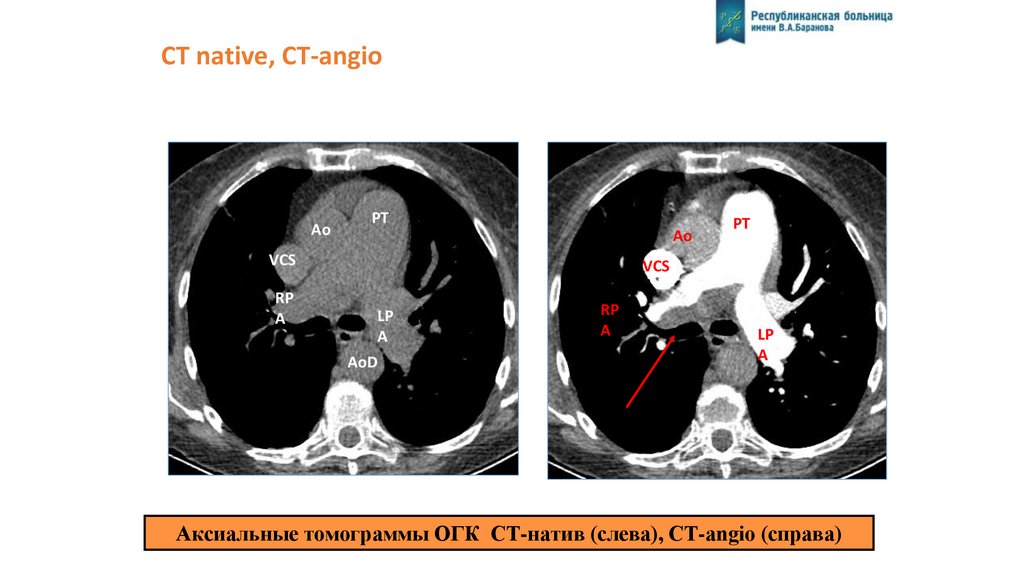

СТ native, CT-angio

Ao

РТ

Ао

VCS

RP

A

LP

AoD

Аксиальные томограммы ОГК CT-натив (слева), CT-angio (справа)